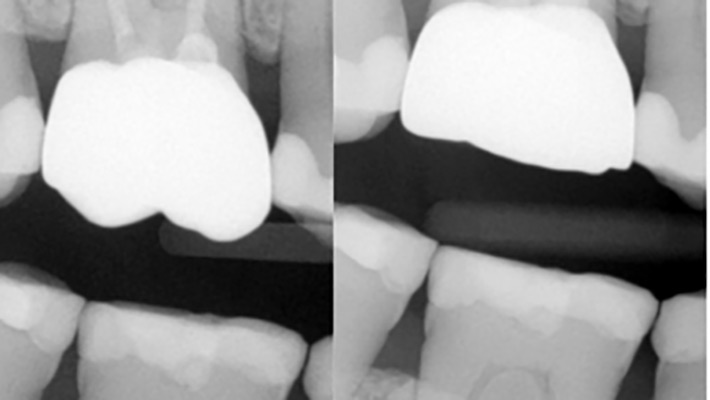

Armamentarium and Techniques For the Immediate Restoration of Endodontically Treated Teeth

Introduction“Control what you can control” -Andre Agassi The standard of practice of mainstream endodontics has traditionally focused on the instrumentation, disinfection and obturation, while paying less attention to the restoration that follows root canal treatment.1 Despite many new advancements over the past six decades – including newer instruments, disinfection technologies and obturating materials – endodontic … Read more